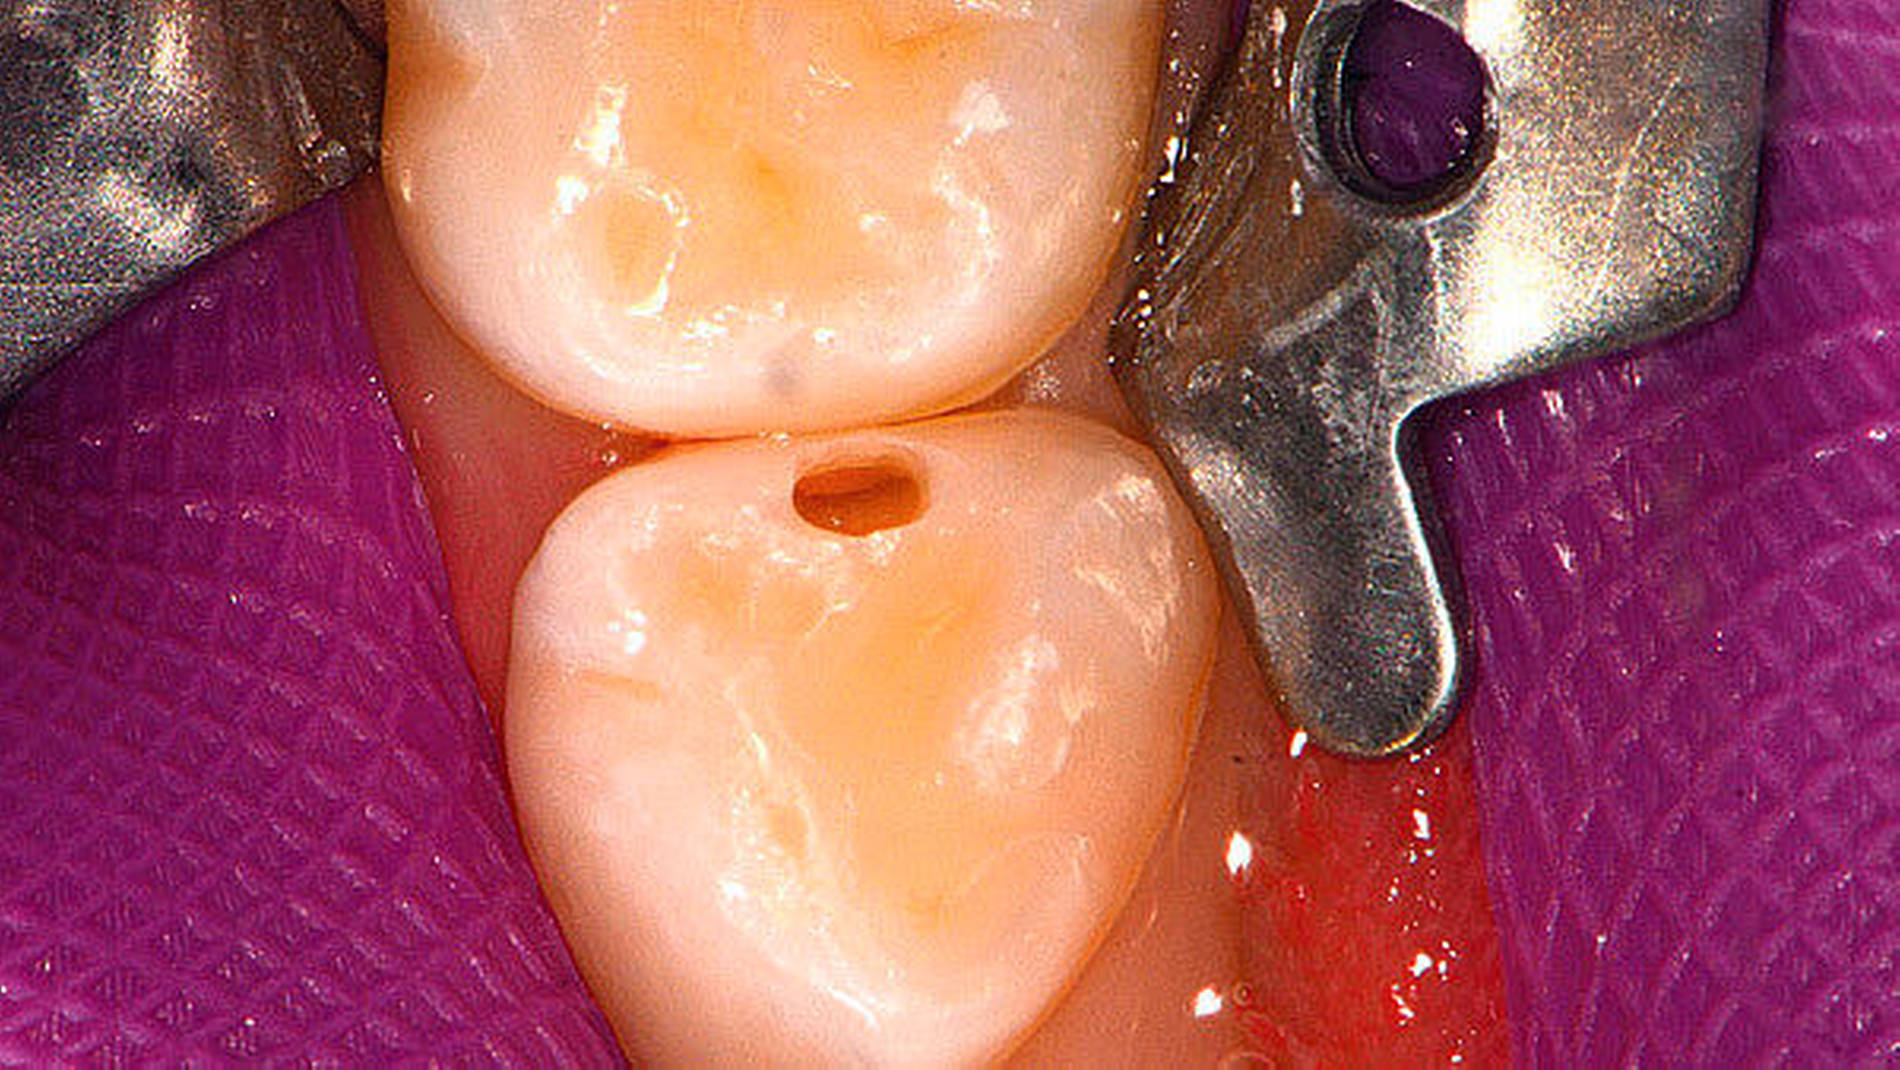

Für die Diagnostik dieser „versteckten“ Läsionen steht außer der rein visuellen Inspektion in der täglichen Praxis vor allem die Anwendung von Bissflügelröntgenbildern zur Verfügung, vor deren Anfertigung aufgrund der Strahlenexposition eine gründliche Risiko-Nutzen-Abwägung verpflichtend ist [RöV; Ekstrand et al., 2015]. Zudem ist für die Anfertigung qualitativ hochwertiger Bilder eine ausreichende Mitarbeit der häufig noch jungen Patienten notwendig. Dies ist im digitalen Röntgenzeitalter selbst mit einem kleinen digitalen Sensor häufig erst ab dem fünften Lebensjahr – selten auch bei jüngeren Kindern – in ausreichender Qualität möglich (Abbildung 1b). Zudem ist für Schmelzläsionen bekannt, dass das Röntgenverfahren zwar eine hohe Spezifität, aber eine nur geringe Sensitivität besitzt.

Sind kariöse Läsionen bereits bis ins Dentin vorgedrungen, ist die Füllungstherapie in der Regel die Therapie der Wahl (Abbildungen 1b und 1c). Bei Läsionen, die die Pulpa erreichen, kann auch bereits eine endodontische Behandlung und gegebenenfalls eine Milchzahnkrone notwendig werden [AAPD, 2012].